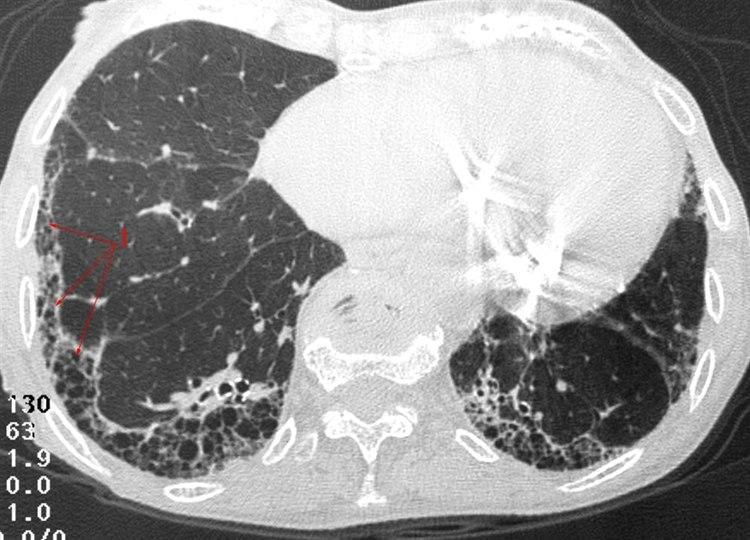

Lungefibrose (HRCT)Lungefibrose er en tilstand med betennelse og økt mengde bindevev (arrvev) i lungene. Arrdannelse er kroppens måte å reparere vevsskade på, ikke bare i lungene, men i hele kroppen. Det er sammenlignbart med et arr i huden etter et skrubbsår. Ved lungefibrose er det unormal arrdannelse i lungeblærene. Når det dannes arr isteden for normalt lungevev, blir gassutvekslingen mellom lunge og blod dårligere enn normalt. Lungene blir stivere og mindre bevegelige, og det arealet som kan brukes til gassutveksling, minker. Har man lett grad av lungefibrose, er det ikke sikkert man merker det på pusten, men jo mer fibrose som dannes, jo tyngre blir det å puste.

Legen foretar en fysisk undersøkelse og tar blodprøver for å komme nærmere diagnosen. Lungefunksjonsprøver (spirometri) kan si mye om hvilken type lungesykdom det dreier seg om. Lungefibrose vil nesten alltid vises på et røntgen-/CT-bilde av lungene. Dersom man fortsatt er i tvil etter røntgen/CT, kan man ta en vevsprøve fra lungene og undersøke denne i et mikroskop.